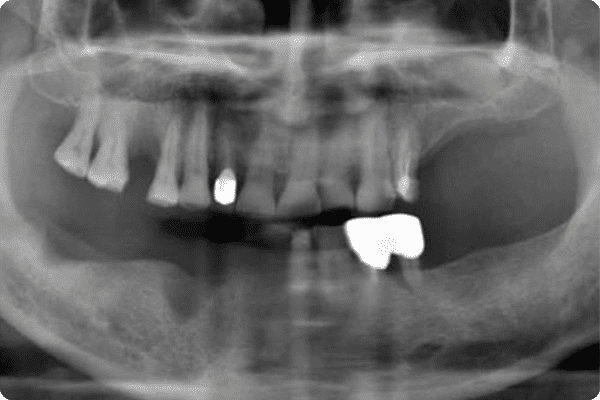

3D CT&디지털 치아 스캐너 정밀 진단-

일반 임플란트

(2D 파노라마)단면으로 치아 상태 및 신경위치를 확인하여

정확한 진단이 어려울 수 있습니다. -

컴퓨터 분석 임플란트

(3D CT)환자의 잇몸뼈와 턱뼈 상태를 3차원 입체 영상으로

정밀하게 진단하여 수술 오차를 줄입니다. -

임플란트 부작용이 걱정돼요CT 촬영을 토대로 제작된 3차원 입체영상을 통해

환자의 치아는 물론 신경구조물에 대한 정밀한 진단이 가능하고

가상수술로 임플란트 식립 할 위치를 파악할 수 있어

부작용 및 신경손상에 대한 우려를 줄일 수 있습니다. -